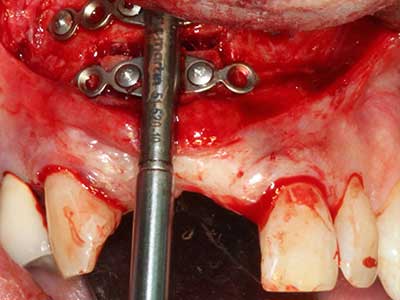

Aplicación: Preparación cerca del nervio

Aplicación: Apicectomía

Si es preciso realizar intervenciones quirúrgicas en las que el hueso está en contacto directo con estructuras sensibles, como son los vasos sanguíneos o los nervios, los instrumentos rotativos presentan un enorme potencial de provocar lesiones iatrogénicas. Así, precisamente en la representación de nervios después de una lesión iatrogénica, o en el transcurso de la lateralización de un nervio para resecciones, reconstrucciones o incorporación de implantes, los equipos piezoeléctricos pueden resultar muy útiles para preparar la tapa ósea y retirar las partes de tejido duro cercanas al nervio (fig. 17-20). Por lo general, un ligero contacto del cordón nervioso con el inserto piezoeléctrico no tiene consecuencia alguna; ahora bien, un procedimiento poco cuidadoso con movimientos tipo sierra o piezas de trabajo sobre la base ósea aún existente puede provocar lesiones nerviosas temporales o incluso permanentes. Con todo, el riesgo de sufrir una lesión de este tipo se considera significativamente inferior que en los casos en los que se utilizan sierras y fresas (Pereira, Gealh et al. 2014).